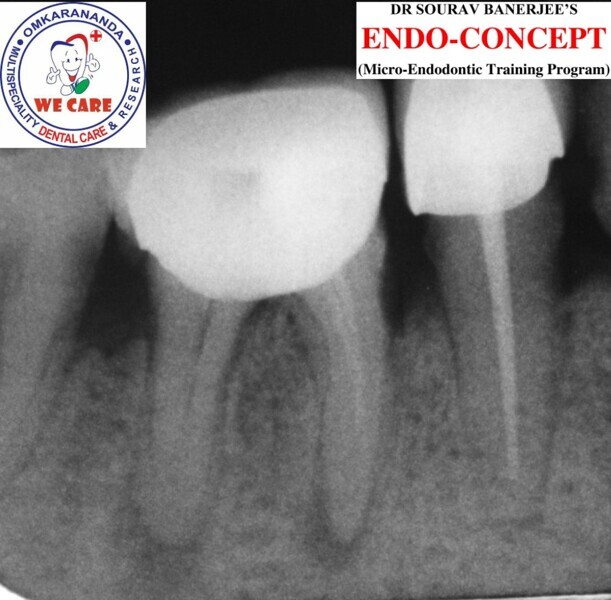

Fig.1a: Pre-op radiograph taken by the referring dentist.

Fig.1b: Pre-op radiograph taken by the author in relation to tooth #46 (January 2019).